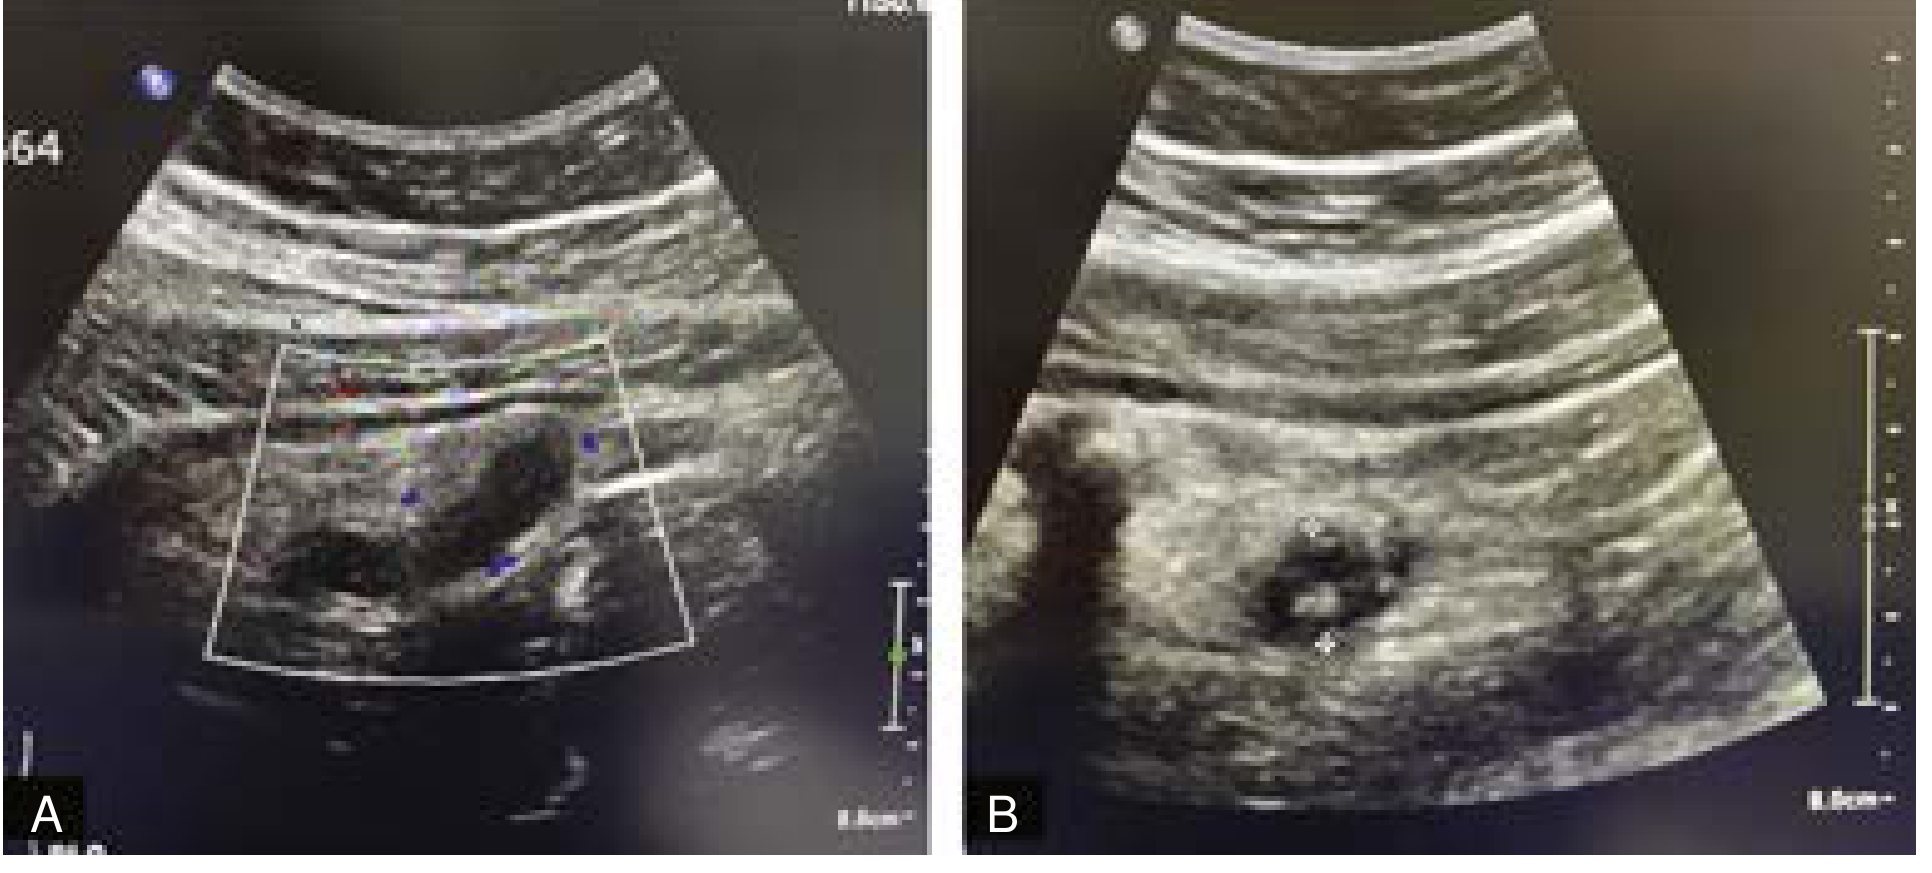

Ultrasound Image — Acute Appendicitis in a Child

Ultrasound showing dilated fluid-filled appendix with appendicolith consistent with acute appendicitis in a 10-year-old child

RLQ ultrasound in a 10-year-old with abdominal pain: (A) dilated fluid-filled tubular structure with increased vascularity; (B) echogenic focus = appendicolith. Both findings consistent with acute appendicitis. — Current Surgical Therapy, 14th ed.